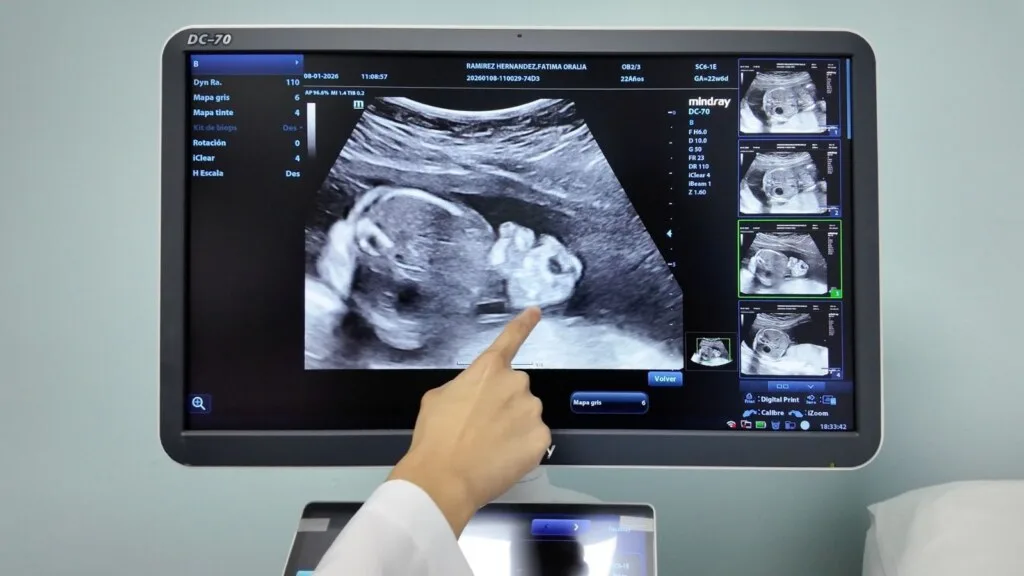

El IMSS Bienestar inauguró la Unidad Nacional de Cirugía Fetal en el Hospital Regional de Alta Especialidad “Dr. Gustavo A. Rovirosa Pérez”, en Villahermosa, Tabasco, un espacio especializado que permite realizar procedimientos de alta complejidad para atender malformaciones congénitas antes del nacimiento.

Como parte de la puesta en marcha de esta unidad, se realizó la primera cirugía fetal por gastrosquisis, una malformación en la que los órganos abdominales del feto se desarrollan fuera de la cavidad abdominal.

El procedimiento se realizó en diciembre, con una duración aproximada de cinco horas, y el nacimiento ocurrió en febrero en condiciones favorables.

La cirugía fetal permite corregir malformaciones congénitas detectadas durante el embarazo mediante técnicas especializadas que requieren monitoreo continuo y la participación coordinada de múltiples especialistas.